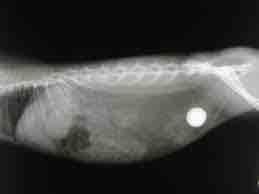

Bauchröntgen:

Für die Suche nach Pathologien der Bauchorgane (Leber, Nieren, Milz, Verdauungssystem etc.)